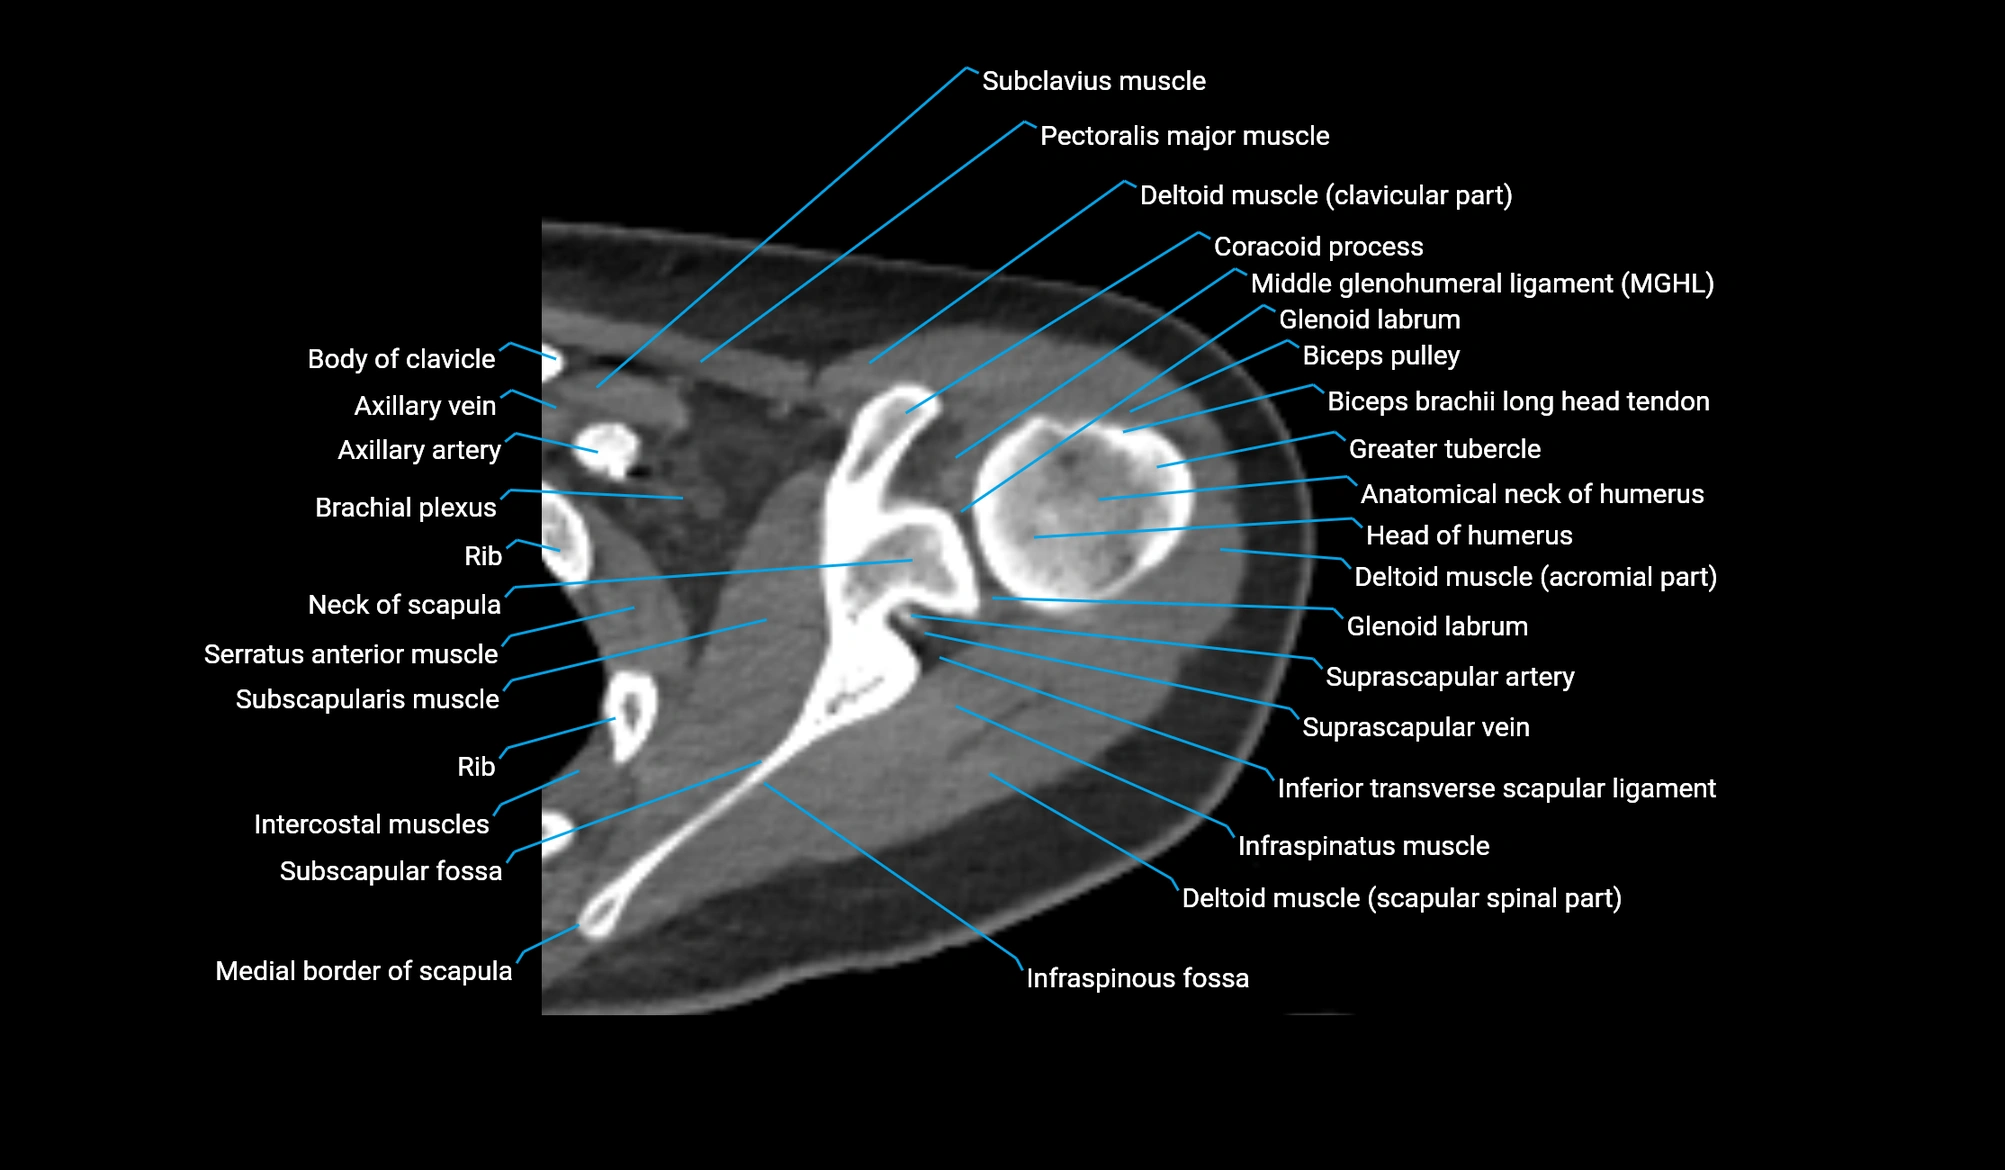

CT image